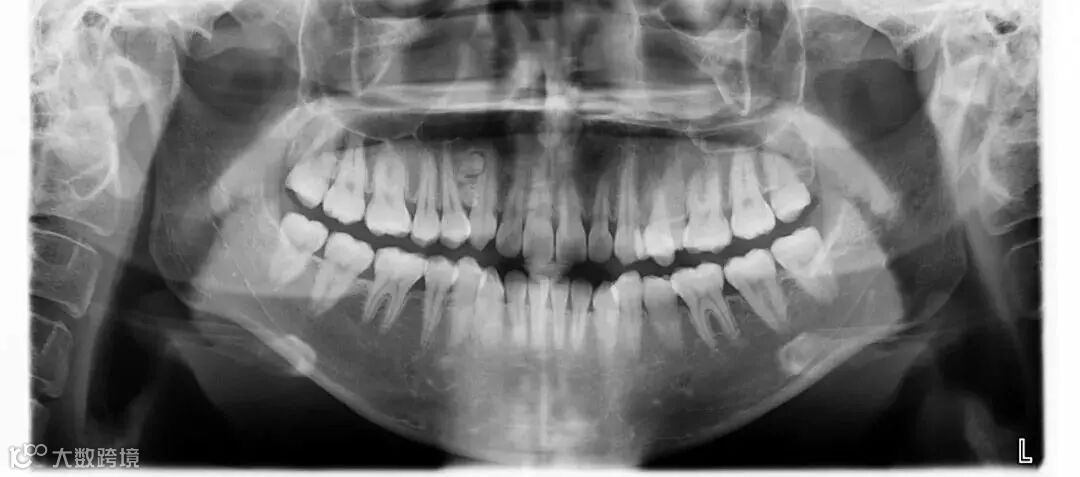

@pengpeng

这是我去做矫正时拍的牙片。不要怀疑,真的是笑着拍的!